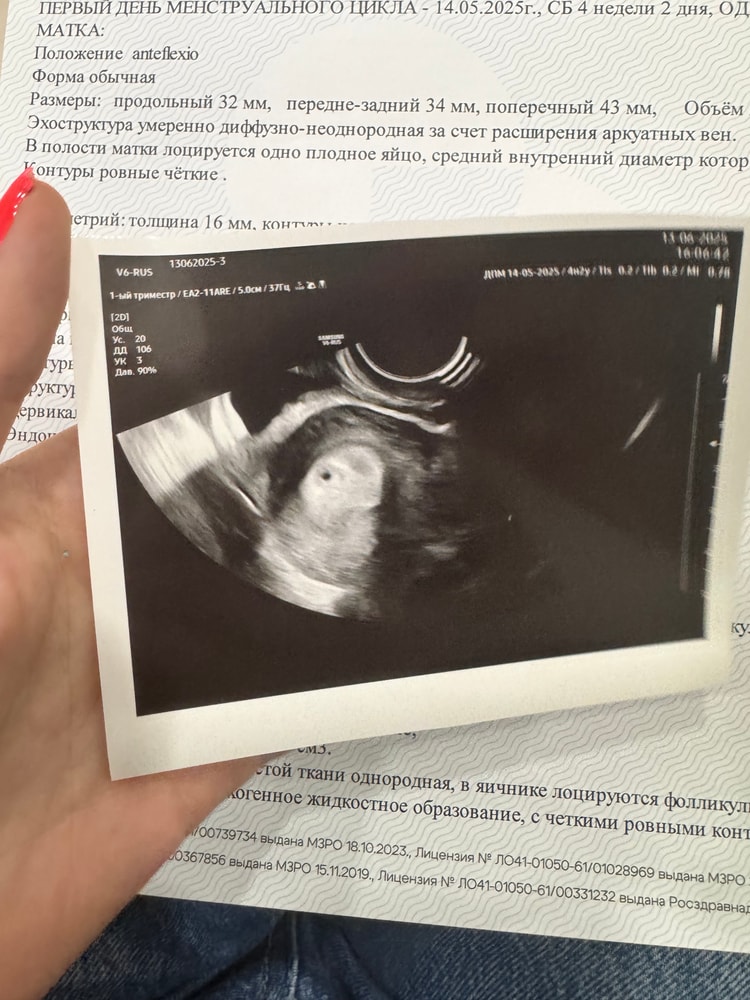

Феникс, не, уже все хорошо, на УЗИ увидели бусинку Изображение

Limonchelka, уже не пойду))) бусинка в матке 🥰